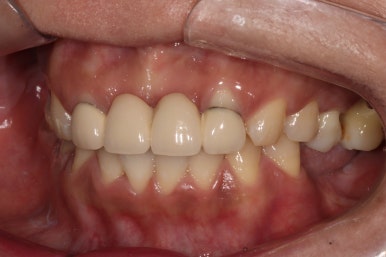

좌측 측면 사진입니다.

제 자리를 잃고 정출되서 내려와 있던 왼쪽 위 어금니들은 제거되었고 (충치도 심했으니깐요)

치아가 하나도 없었던 아래쪽엔 스트라우만 임플란트를 이용하여 완전히 재건된 모습을 확인할 수 있습니다.

애당초 잇몸뼈가 내려가 있으신 상태였기에, 치아가 다소 길어보일 순 있으나.. 이 정도면 상당히 준수!